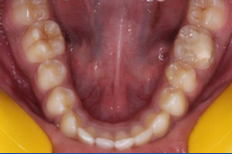

检查发现右上颌第一磨牙缺失,右下颌第一磨牙伸长并舌倾,上颌垂直向修复空间不足。

考虑到美观、舒适度、治疗时间,计划在下颌第一磨牙颊舌侧植入微型种植体,配合弹簧矫正下颌第一磨牙。前后治疗时间为45天。45天后三维扫描分析软件分析矫正情况,以邻近第二磨牙近中颊尖和第二前磨牙颊尖连线为基准,下颌第一磨牙颌面已压低1.8mm;以第二磨牙和第二前磨牙颊舌尖连线为基准,下颌第一磨牙颊向移动2.3mm。